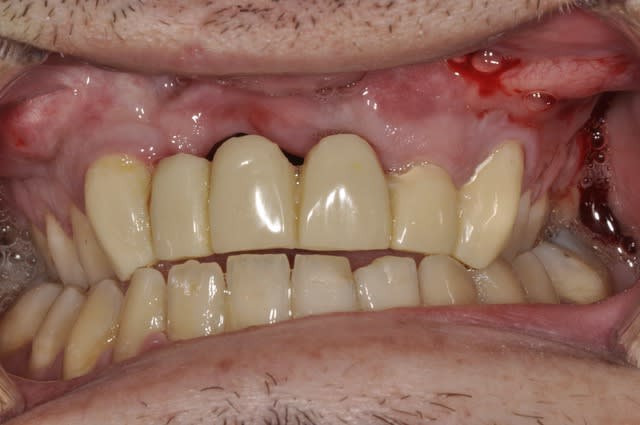

Bridge sur patient ayant une fente faciale.

J'ai du déposé le bridge ailette et faire l'extraction de 11 et 21 pour cause resorption externe.

Puis bridge sur dent vivante avec 13/22/23 comme pilier.

J'ai revu le patient au bout d'un an.

Hygiéne approximative mais pas évidente en même temps.

Je vous ai mis des photos du labo, puis 1 semaine après la pause et enfin celles de la semaine dernière.